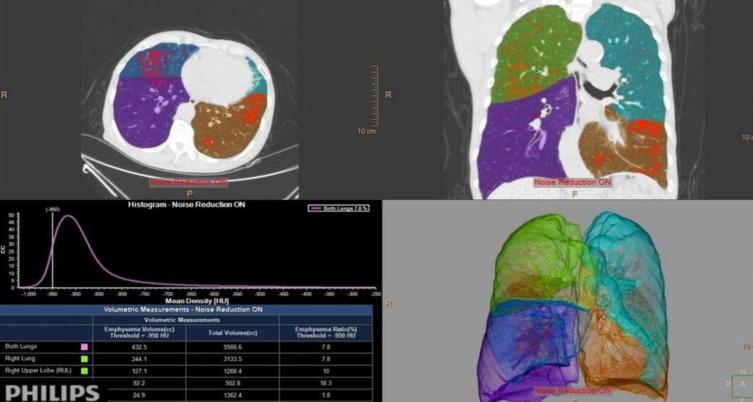

Patients with asthma (n=48), COPD (n=52), and ACO (n=30) and controls (n=54) who completed pulmonary function tests and HRCT scans were retrospectively enrolled in our study. Quantitative CT analysis software was used to assess emphysema (LAA%), airway wall dimensions (wall area (WA), luminal area (LA), and wall area percentage (WA%)), and air trapping ((relative volume change of -860 HU to -950 HU (RVC) and the expiration-to-inspiration ratio of the mean lung density (MLD)). Differences in pulmonary function and HRCT parameters were compared among the groups. Spearman correlation analysis and regression analysis were utilized to explore structure‒function relationships.

The LAA% in COPD and ACO patients was significantly greater than that in asthmatic patients and controls. The WA% and WA in COPD and ACO patients were greater than those in controls, whereas the WA% and LA between asthmatic patients and controls reached statistical significance. The RVC levels decreased in the following order: ACO, COPD, and asthma. RVC independently predicted FEV1% in asthmatic patients; LAA% and MLD in COPD patients; and LAA%, WA% and RVC in ACO patients.

Comparable emphysema was observed in patients with COPD and ACO but not in asthmatic patients. All patients exhibited proximal airway remodeling. The bronchi were thickened outward in COPD and ACO patients but are thickened inward in asthmatic patients. Furthermore, air trapping in ACO patients was the most severe among all the groups. Indirect lung densitometry measurements might be more predictive of the degree of airflow limitation than direct airway measurements in obstructive airway diseases.